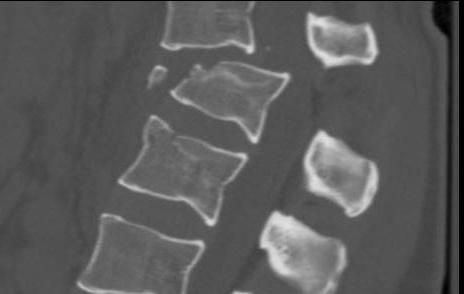

X-ray

- pedicle widening on AP

- posterior body height decreased on lateral < 50%

CT scan

- xray only 25% accurate distinguishing compression from burst

- indicated if anterior body height < half posterior body height

- i.e. > 50% anterior wedging

- assess integrity of middle column / look for retropulsed fragments